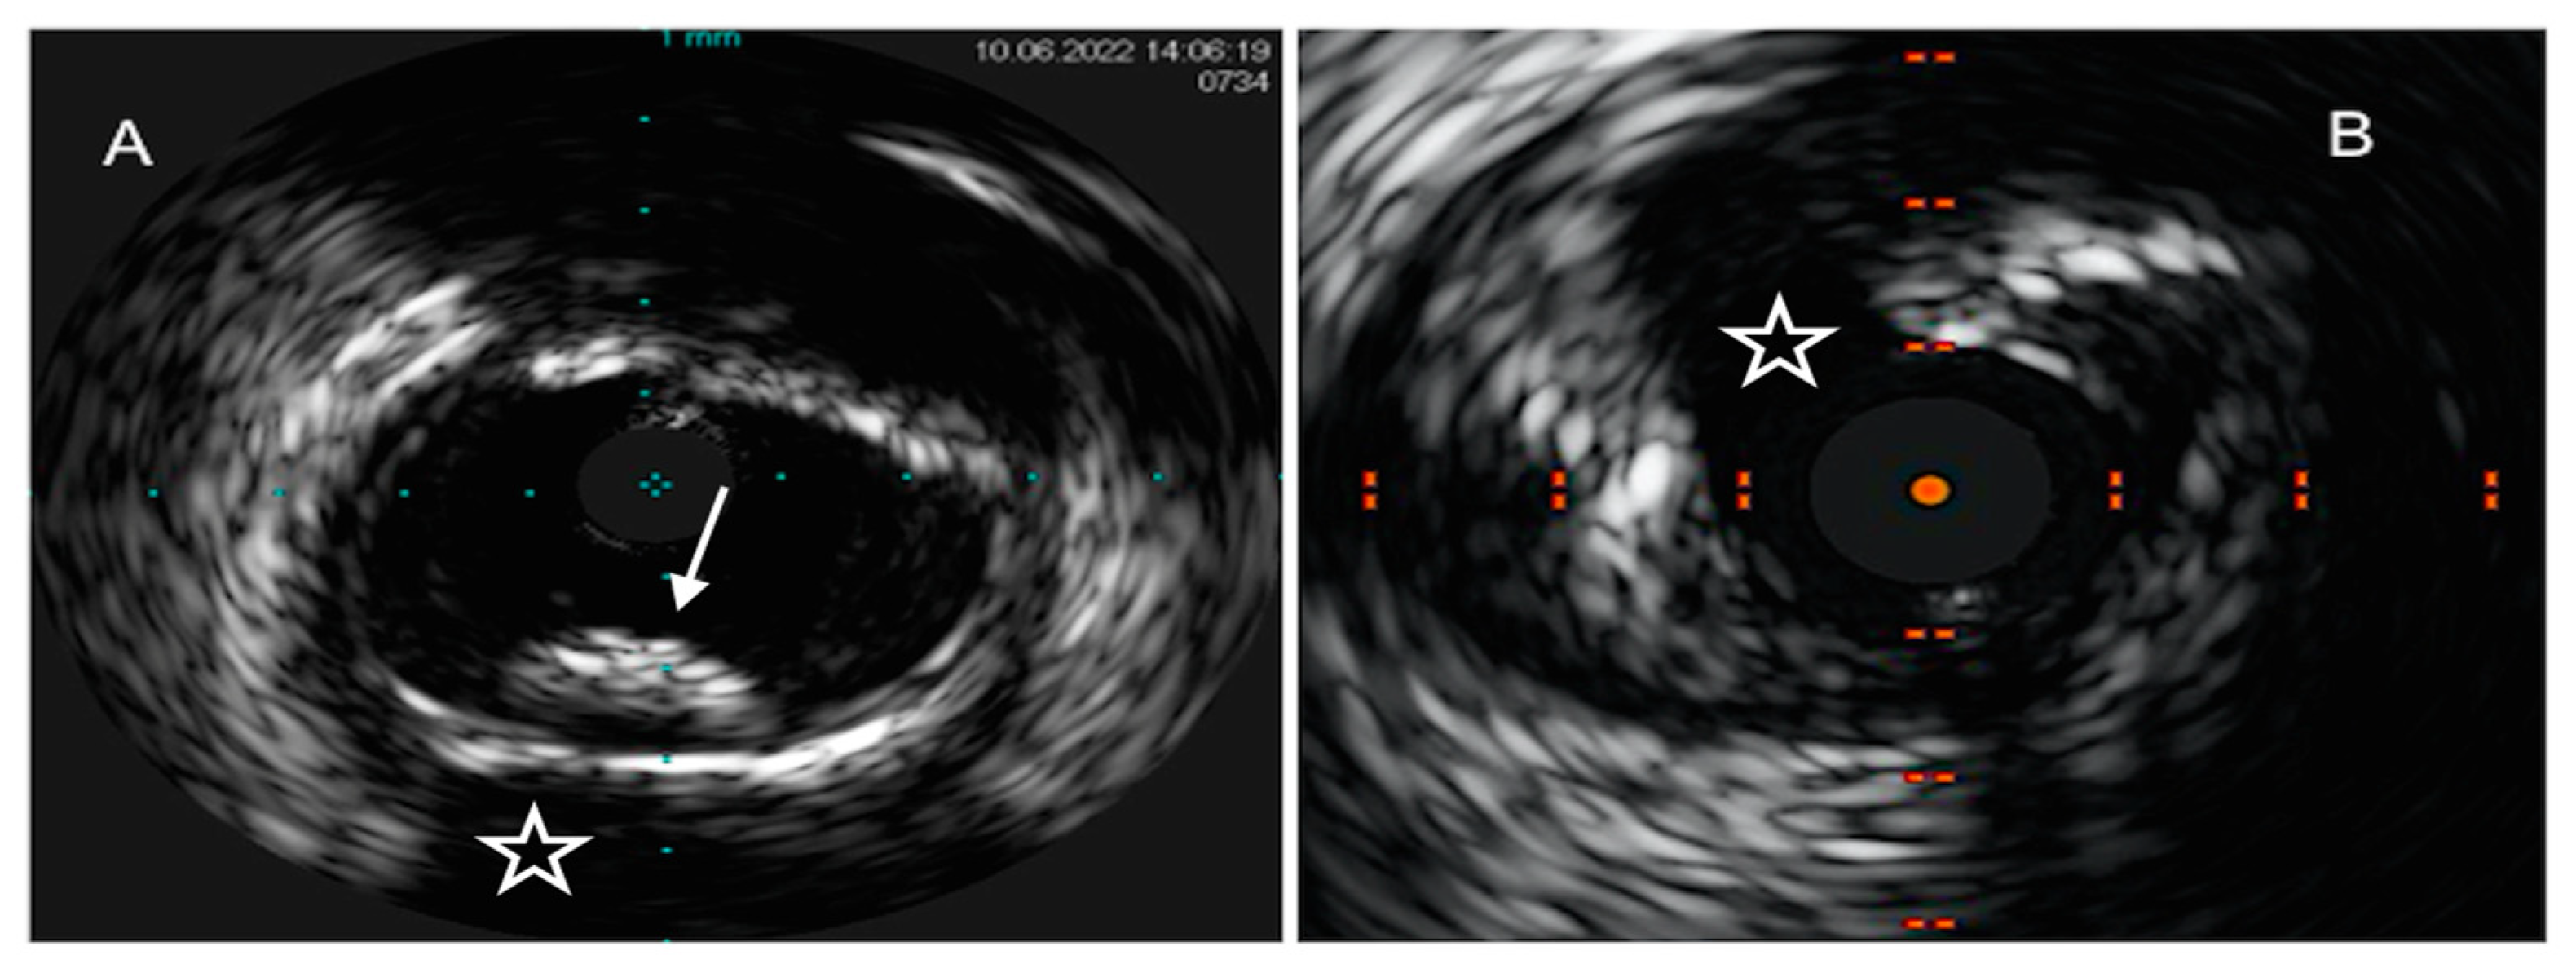

- Sheth, T.N.; Pinilla-Echeverri, N.; Mehta, S.R.; Courtney, B.K. First-in-Human Images of Coronary Atherosclerosis and Coronary Stents Using a Novel Hybrid Intravascular Ultrasound and Optical Coherence Tomographic Catheter. JACC Cardiovasc. Interv. 2018, 11, 2427–2430. [Google Scholar] [CrossRef]